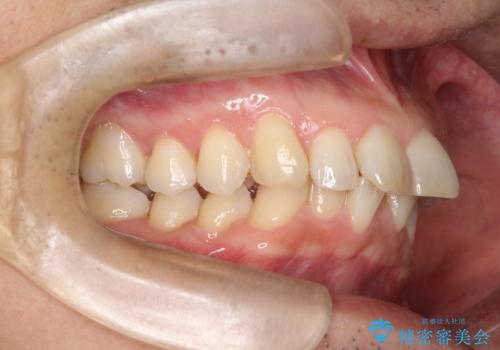

【インザライン】前歯の凸凹を治したい

- 前歯の凸凹を主訴に来院されました。

下顎位が右方に変異しており、外科矯正も提案しましたが患者様は希望されず、インビザラインにて治療を完了しております。

叢生のスペースを確保するために、臼歯部の遠心移動を行っています。

今回の治療計画は上顎の正中を顔と揃えることを優先しています。